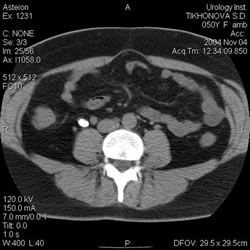

Компьютерная

томография: |

|